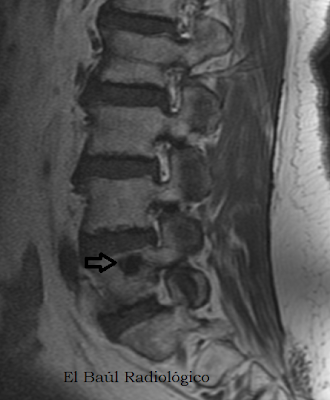

FIGURA 1) Imagen FSE-T1. Lesión hipointensa, redondeada, de contornos bien delimitados, situada en el cuerpo vertebral L1. Enostosis

(A weigthed FSE-T1 MRI of lumbar spine. Hypointense lesion, rounded, with well-defined contours, located in the vertebral body of L1 Enostosis).